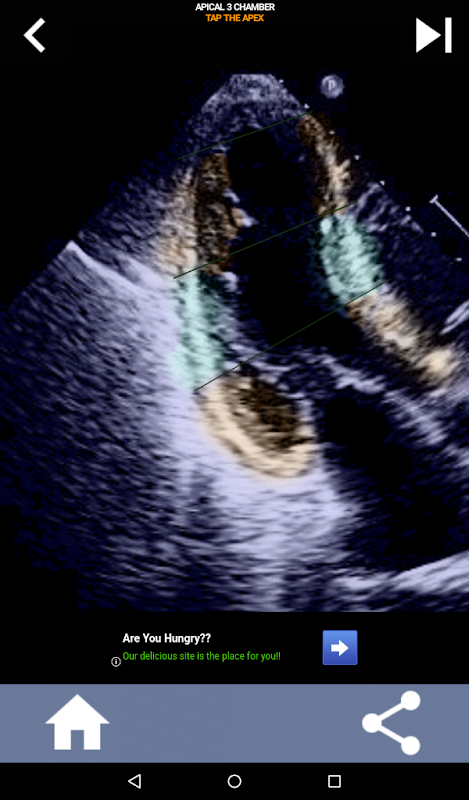

มันเป็นสิ่งสำคัญสำหรับ echocardiographers อัลตราซาวนด์ที่จะเรียนรู้การแบ่งส่วนหัวใจอเมริกันสมาคมหัวใจช่องซ้ายเป็น 17 ส่วนซึ่งเป็นมาตรฐานที่ใช้กันอย่างแพร่หลายโดยรังสีถ่ายภาพอื่น ๆ เช่นการถ่ายภาพด้วยคลื่นสนามแม่เหล็ก, การทดสอบนิวเคลียร์หัวใจ ฯลฯ ของกลุ่มและฟังก์ชั่นที่ได้รับผลกระทบ หลายครั้งที่คนอ่านเสียงสะท้อนของคุณจะถามว่า "คุณเห็นอะไร" และการตอบกลับด้วยตำแหน่งที่แน่นอนของพื้นที่ที่ได้รับผลกระทบเป็นสิ่งที่คาดหวัง

แอพนี้มีมุมมอง echo ทั้งหมดที่แสดง myocardium ที่แบ่งกลุ่ม AHA และจะตอบคำถามคุณเพื่อแตะส่วนที่ถูกต้อง โดยส่วนตัวแล้วฉันพบว่าการสอบย่อยแบบทำซ้ำได้ผลดีที่สุดสำหรับฉันเมื่อฉันต้องการเรียนรู้ / จดจำหัวข้ออย่างรวดเร็ว หากคุณเป็นนักเรียนอัลตราซาวนด์ที่เรียน echo / TTE ฉันคิดว่านี่จะเป็นส่วนเสริมที่ยอดเยี่ยมสำหรับการเรียนของคุณ